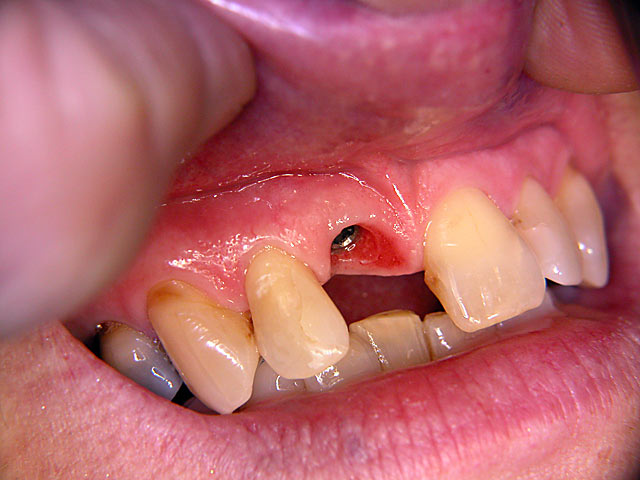

Die folgenden Patientenfälle sollen Ihnen einen Einblick in die Möglichkeiten der modernen Implantation geben.

Sofort-Implantation: